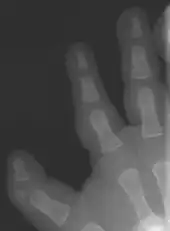

| Finger-like appearance | |

Triphalangeal thumb (TPT) is a congenital malformation where the thumb has three phalanges instead of two. The extra phalangeal bone can vary in size from that of a small pebble to a size comparable to the phalanges in non-thumb digits. The true incidence of the condition is unknown, but is estimated at 1:25,000 live births.[1] In about two-thirds of the patients with triphalangeal thumbs, there is a hereditary component.[2] Besides the three phalanges, there can also be other malformations. It was first described by Columbi in 1559.[3]

The triphalangeal thumb has a different appearance than normal thumbs. The appearance can differ widely; the thumb can be a longer thumb, it can be deviated in the radio-ulnar plane (clinodactyly), or thumb strength can be diminished. In the case of a five-fingered hand it has a finger-like appearance, with the position in the plane of the four fingers, thenar muscle deficiency, and additional length. There is often a combination with radial polydactyly.